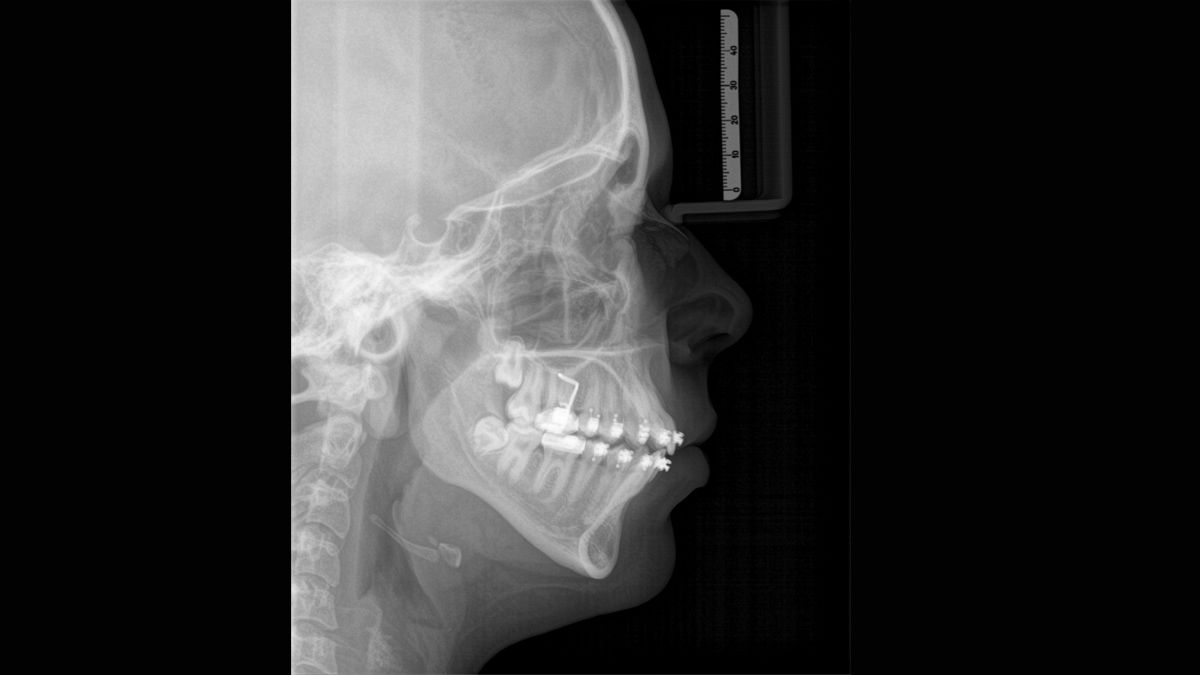

Tecnología Sharp Layer (SL)

La tecnología SL le permite generar multiples imágenes durante una única rotación. Los fragmentos con mejor enfoque se combinan automáticamente para formar una imagen de rayos X con nitidez incomparable (ideal para observar piezas multiradiculares).

Algoritmo de software ASTRA

ASTRA mejora considerablemente la calidad de las imágenes panorámicas 2D y cefalométricas. Este algoritmo de reconstrucción estructurado anatómicamente genera una imagen con mayores contrastes sin la aparición de bordes indefinidos.